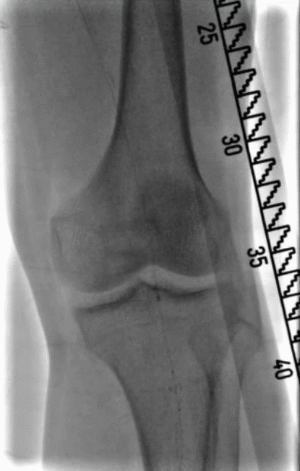

术前CTA:左侧股浅动脉重度钙化,双髂动脉重度狭窄。

图片

术前CTA:右侧股浅动脉多节段重度狭窄、闭塞。